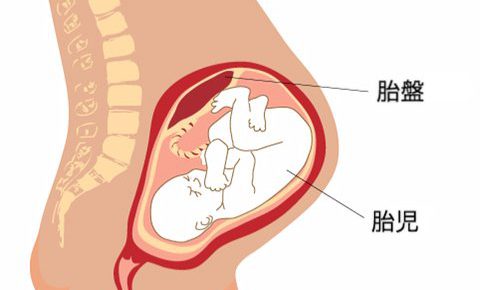

臓器

臓器

臓器

臓器

臓器

臓器

臓器

臓器

臓器

臓器

臓器

臓器

臓器

臓器

臓器

臓器